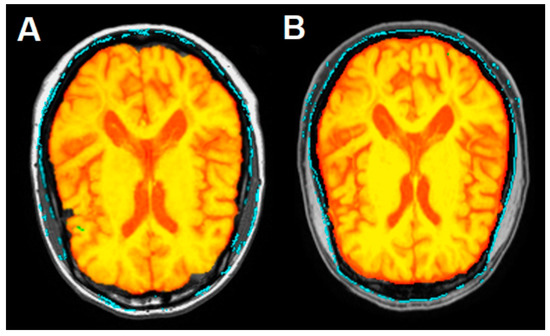

Figure 1.

Magnetic resonance imaging on the short tau inversion recovery (STIR) sequence of the cervical spinal cord, affected by a demyelinating lesion at the second and third metamer before (A) and after (B) DFPP treatment. Note the reduction in the size of the lesion in comparison to the pre-treatment image. Axial brain magnetic resonance imaging on the fluid attenuated inversion recovery (FLAIR) sequence shows the periventricular lesion load before (C) and after (D) DFPP treatment. Red arrows evidence the brain and spinal cord lesions.

These lesions, partially confluent and not exceeding three metamers in length, were not associated with tumefactive cervical shape and fulfilled the radiological criteria for MS lesions, as expected. No new brain lesions were detected and a total intracranial volume (TIV) of 1328.8 mL was calculated using Siena software. Thus, the diagnosis of steroid-refractory relapsed MS on Fingolimod treatment was posed, DFPP therapy was indicated, and FTY was discontinued. In Figure 1C it could be also glimpsed two subcortical hyperintense left frontal areas, resulting from enhancing lesions at the disease onset. The demonstration of these lesions assumes an important diagnostic role in the present case, and they are better represented in Figure 2.

The control MRI performed before the department discharge showed detectable reduction in the volume of cervical lesions, as depicted in Figure 1B, but a stable brain lesion load (Figure 1D).